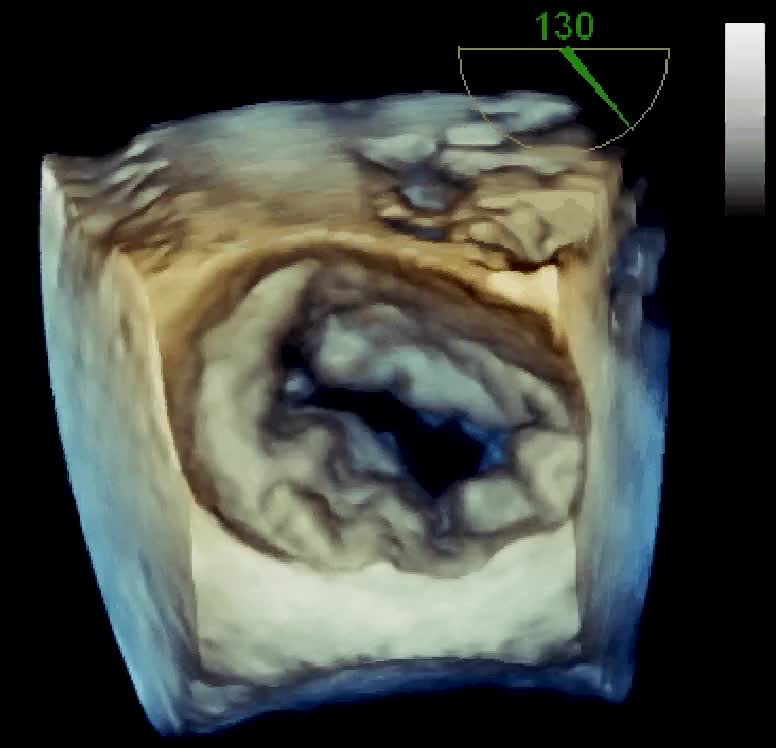

Insufficienza mitralica da rottura cordale

Autore:

Daniela Torta